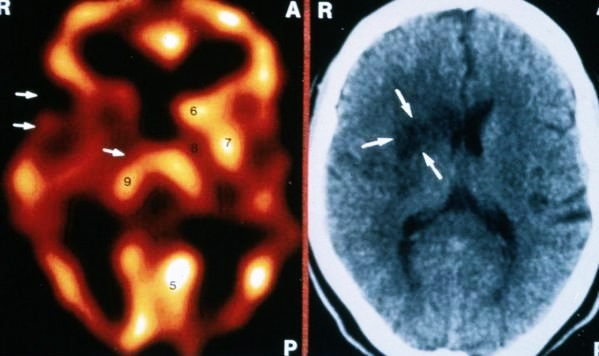

Спасение пациентов начинается с экстренной томографии. Это обследование помогает определить характер инсульта и назначить правильное лечение. К современным методам точной диагностики относят МРТ (магнитно-резонансную) и КТ (компьютерную томографию).

Прежде чем начать вводить препараты, необходимо диагностировать тип инсульта: это тромб или кровоизлияние. Каждый имеет характерные внешние признаки. В последнем случае, если ввести препарат, рассасывающий тромб, человек умрет через минуту. Поэтому пациента необходимо доставить в ту клинику, где есть аппарат МРТ или КТ, чтобы иметь точную картину зон пораженных полушарий.